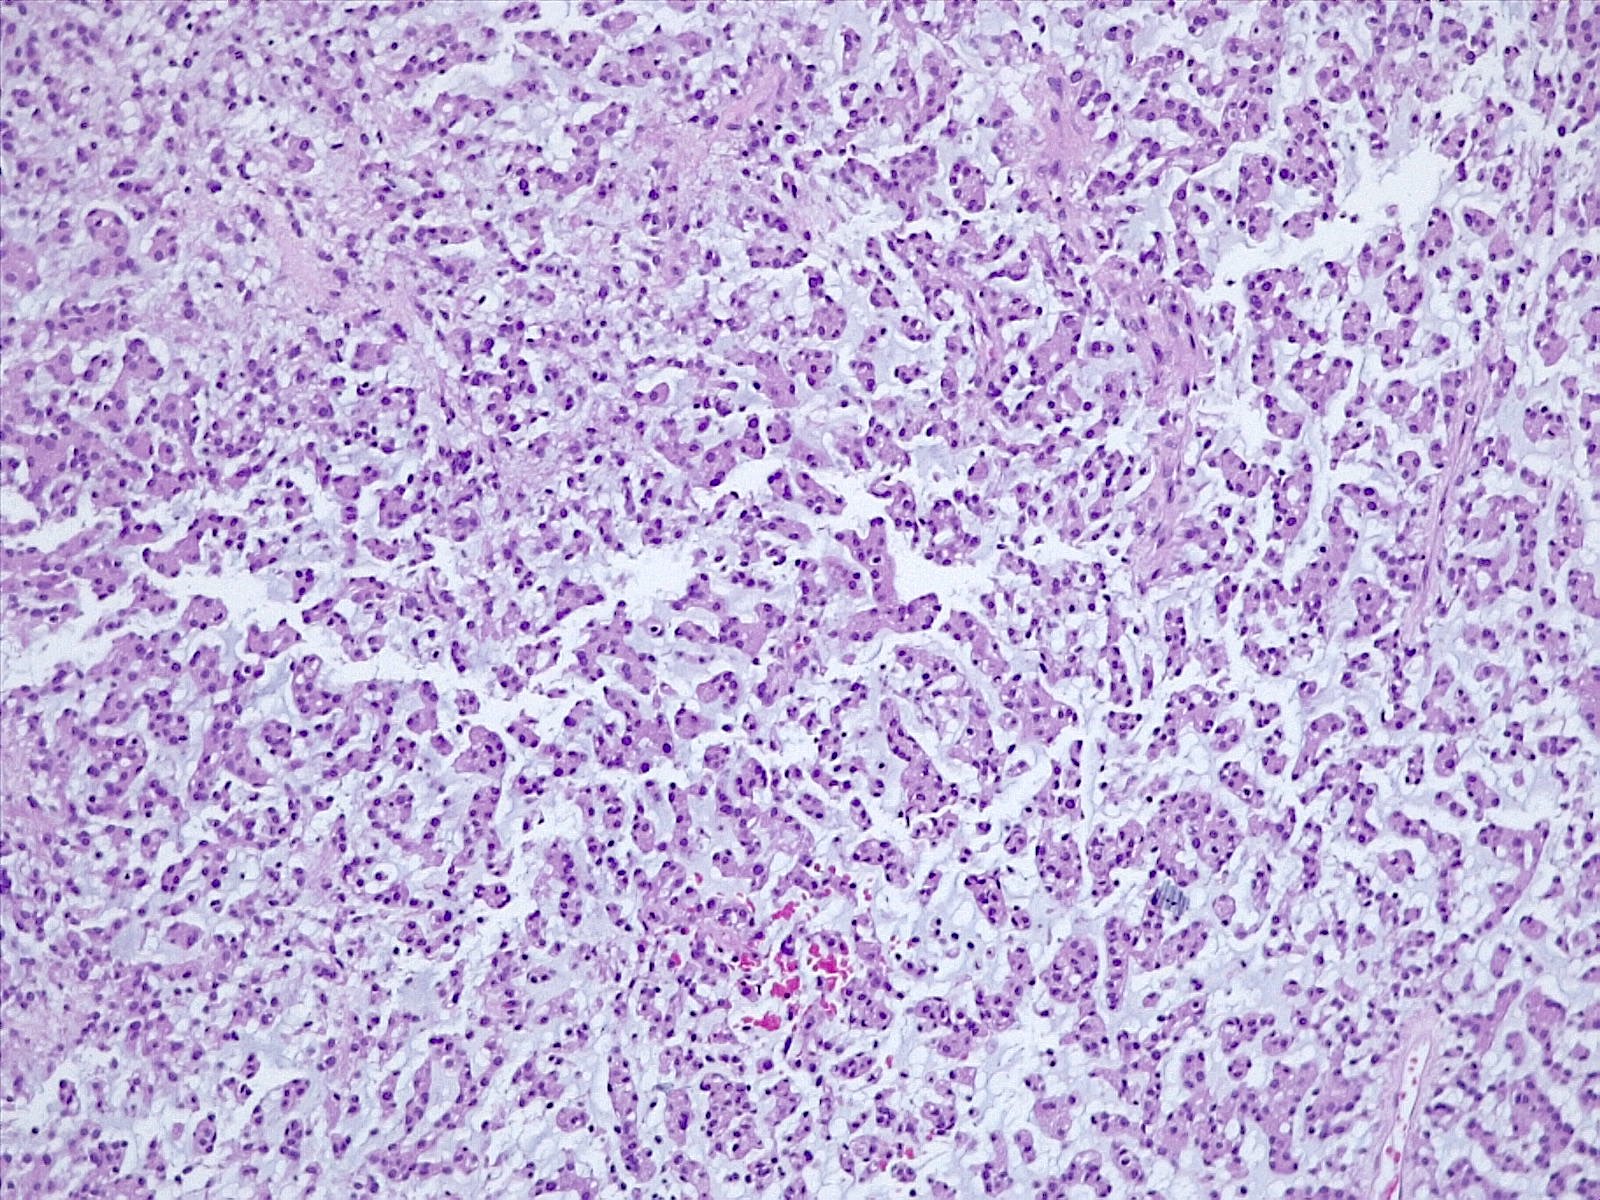

- Histologically reminiscent of chordoma, consisting of epithelioid cells or spindle cells (often partly vacuolated) that are arranged in cords within a pale basophilic myxoid matrix (Am J Surg Pathol 2000;24:899, J Neurooncol 2010;100:465, Histopathology 2013;62:1002)

- Chordoid morphology must be the predominant pattern for diagnosis of chordoid meningioma and CNS WHO grade 2 designation

- Interspersed areas of more typical meningioma are frequent but pure chordoid cases may be seen (Am J Surg Pathol 2000;24:899, J Neurooncol 2010;100:465, Histopathology 2013;62:1002)

- Atypical features may be seen, including mitoses, brain invasion, spontaneous necrosis, macronucleoli, increased cellularity, sheeting or small cells with a high N:C ratio (Am J Surg Pathol 2000;24:899, Acta Neuropathol Commun 2022;10:56, Histopathology 2013;62:1002)

- Lymphoplasmacytic infiltrate in 59.5% (Am J Surg Pathol 2000;24:899)